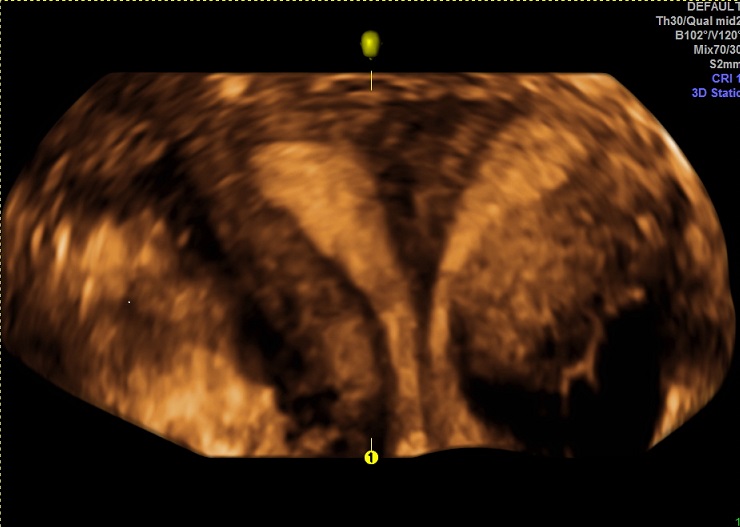

二维超声:观察子宫及双侧卵巢形态和结构变化,对子宫、输卵管、卵巢及盆腔的疾病做基础性排查。